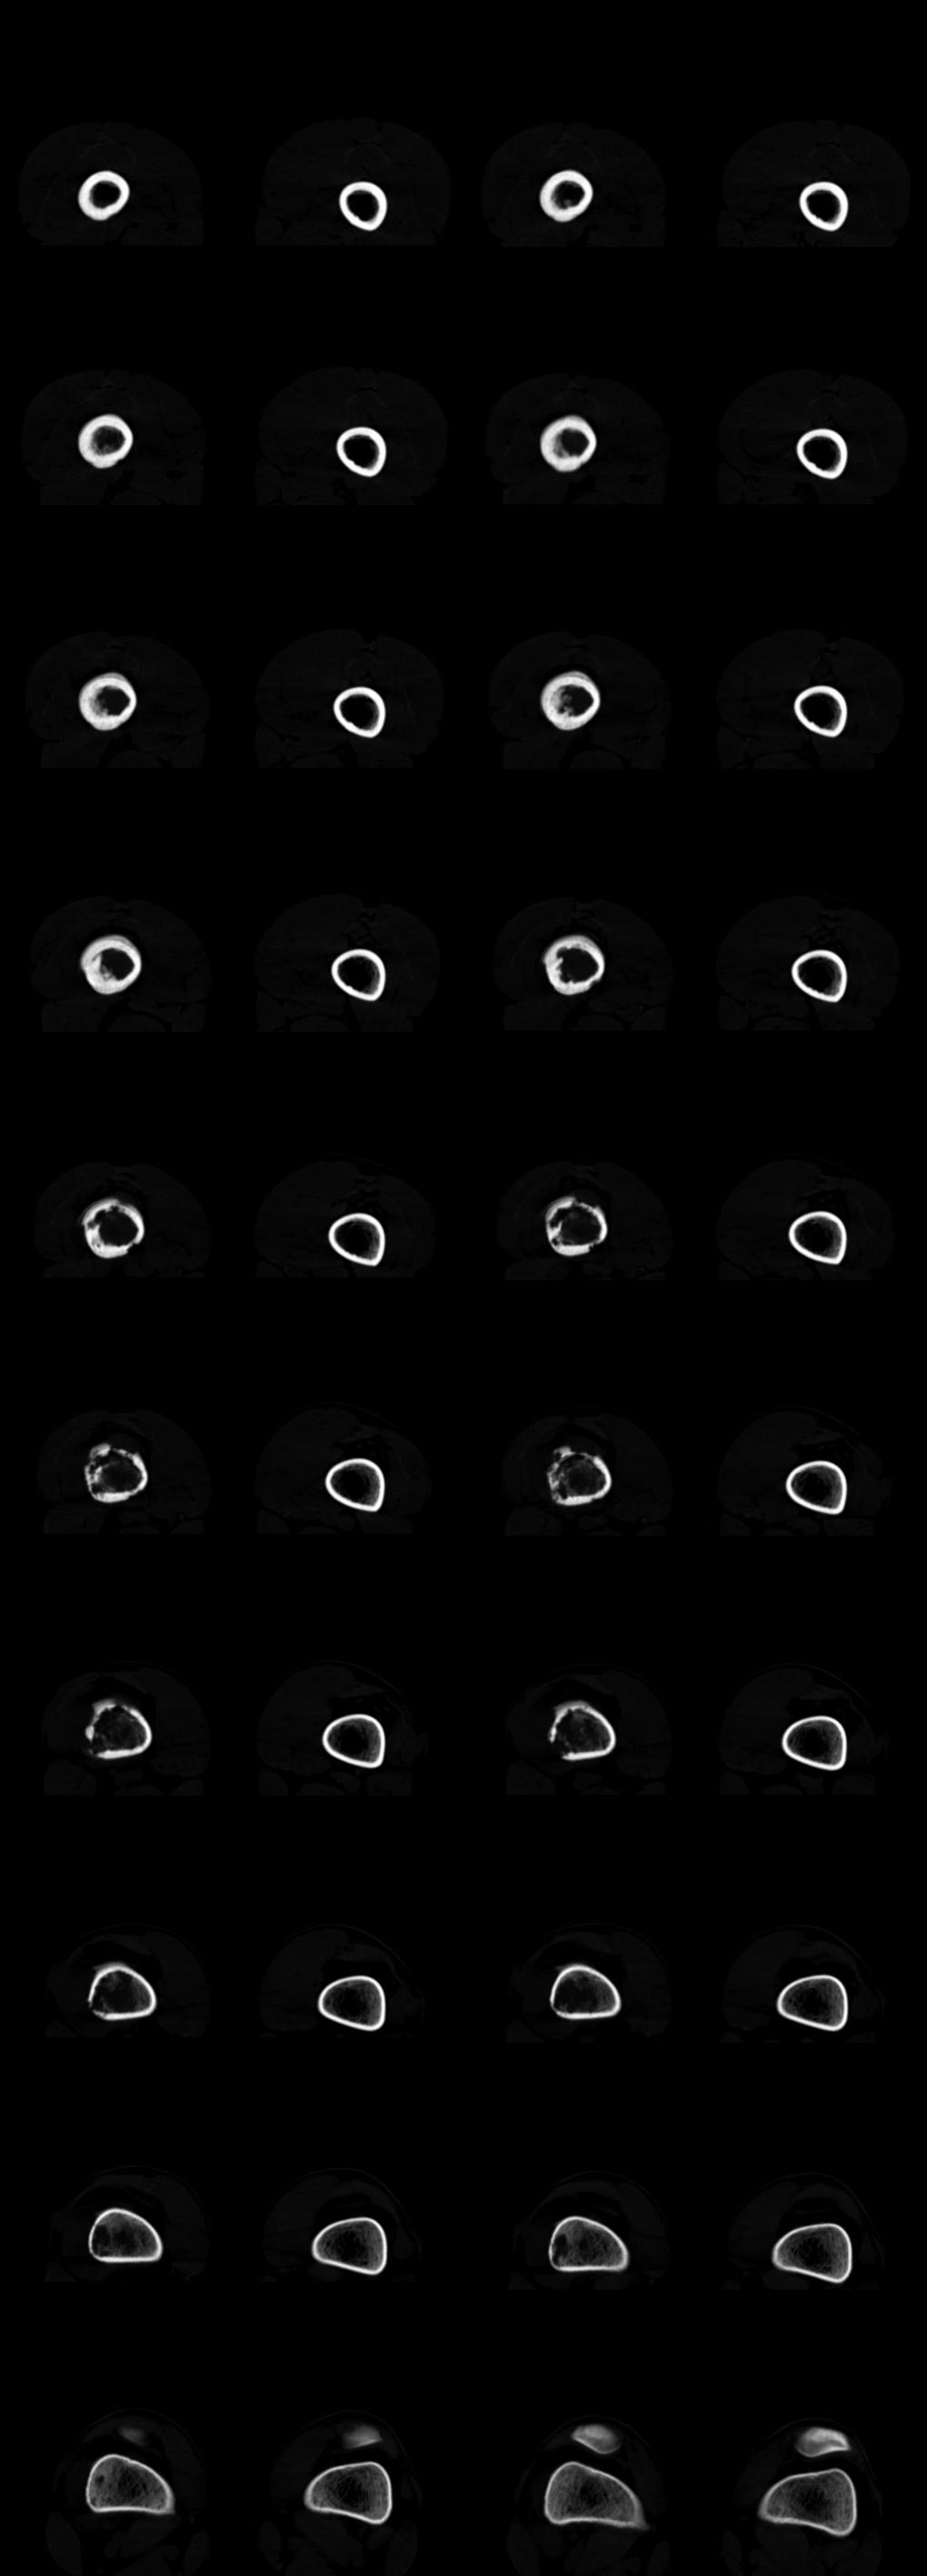

患者年龄、发病部位、ct表现:溶骨性骨质破坏、柳絮状肿瘤骨形成、骨膜增生、软组织肿块(虽然小)

x线对骨膜反应及骨膜三角显示好,建议上传平片。同意骨肉瘤诊断(ct对骨质破坏,肿瘤骨及软组织肿块显示较好)。